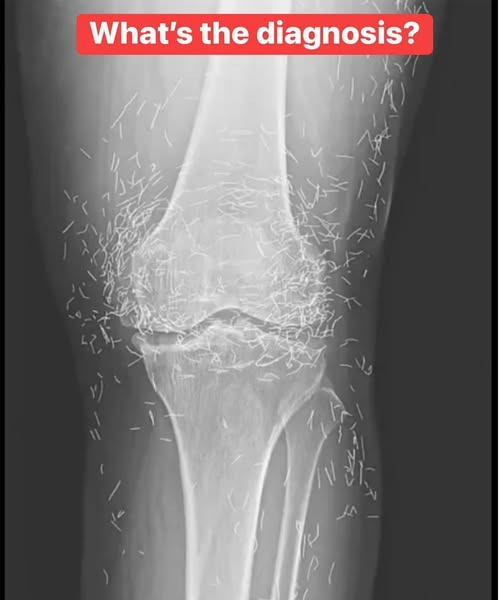

X-Ray Reveals Gold Acupuncture Needles in Woman’s Knees – What Really Happened

When doctors examined the X-ray of a 65-year-old woman in South Korea with severe knee pain, they didn’t just see signs of osteoarthritis. They saw something unexpected: hundreds of tiny metallic fragments embedded in her knee joints. But contrary to viral headlines claiming “hundreds of gold needles,” the truth is more nuanced — and medically … Read more